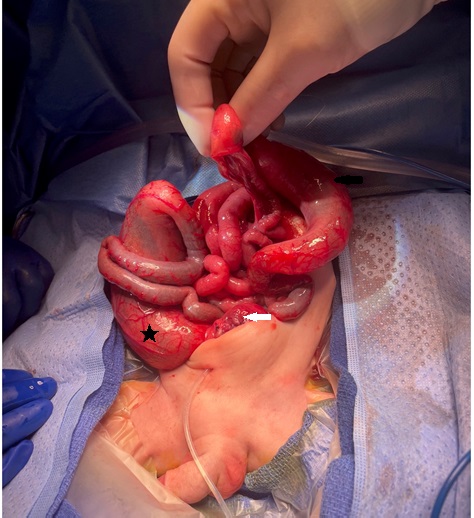

Intraoperative photo showing the dilated cecum and ascending colon (black arrow), with an abrupt change in caliber at the transverse colon. Pouch colon (black asterisk) and urinary bladder (white arrow) are also visible.